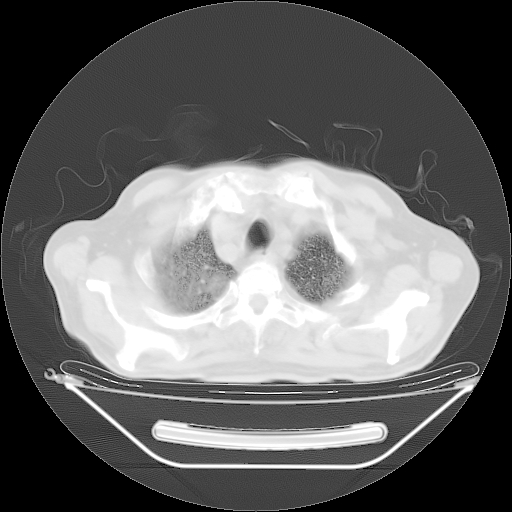

今天复查肺部CT,发现双肺广泛磨玻璃样改变。所以我把3月19日和5月9日相隔50天的肺部CT上传。请大家会诊。

2009年3月19日肺部CT片。

5月9日肺部CT(在4月27日齐鲁医院肺部CT描述部分肺组织磨玻璃样改变,12天后肺组织广泛磨玻璃样改变)

大致读了系列胸部CT:纵隔窗无明显异常,肺窗:从4、27至今:主要是双肺中下野外带可见毛玻璃样改变,目前处于急性肺泡炎阶段,至于原因考虑1、结替组织或胶原血管性疾病所致?2、恶性疾病如恶组在肺部所致的表现或细支气管肺泡癌?3、药物或其它原因如肺蛋白沉着症所致肺泡炎目前不太可能?总之,明天就去请我院的呼吸科、感染科、血液科和临免专家会诊哈。